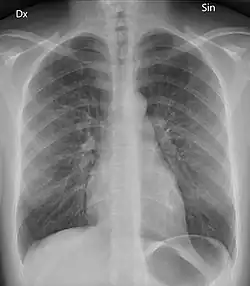

Chest

Chest radiographs are used to diagnose many conditions involving the chest wall, including its bones, and also structures contained within the thoracic cavity including the lungs, heart, and great vessels. Conditions commonly identified by chest radiography include pneumonia, pneumothorax, interstitial lung disease, heart failure, bone fracture and hiatal hernia. Typically an erect postero-anterior (PA) projection is the preferred projection. Chest radiographs are also used to screen for job-related lung disease in industries such as mining where workers are exposed to dust.[12]

For some conditions of the chest, radiography is good for screening but poor for diagnosis. When a condition is suspected based on chest radiography, additional imaging of the chest can be obtained to definitively diagnose the condition or to provide evidence in favor of the diagnosis suggested by initial chest radiography. Unless a fractured rib is suspected of being displaced, and therefore likely to cause damage to the lungs and other tissue structures, an X-ray of the chest is not necessary as it will not alter patient management.